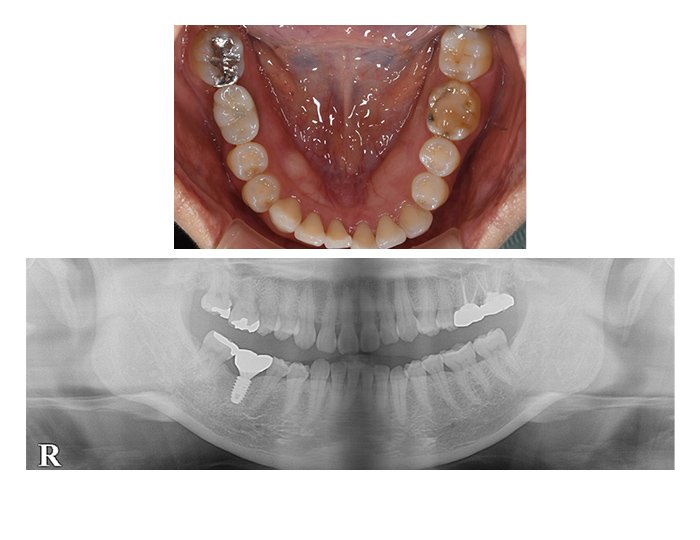

症例02 奥歯のインプラントと骨造成(男性、期間9カ月)

BEFORE(術前)

AFTER(術後)